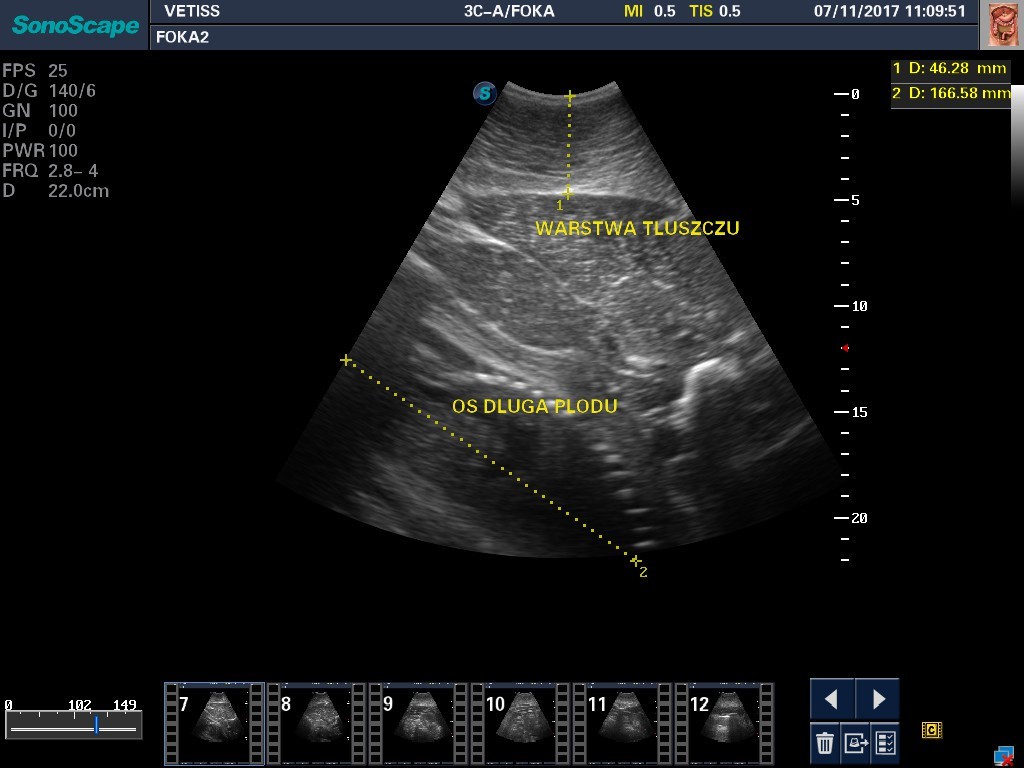

W helskim fokarium już niedługo na świat przyjdą dwa focze szczenięta. Poród planowany jest na przełomie lutego i marca. Gdy młode foki dorosną, dołączą do tych dziko żyjących w morzu. To efekt trwającego od lat 90. programu odtworzenia populacji fok w Bałtyku.

Ciąża u foki trwa 11,5 miesiąca, zawsze jest pojedyncza. Po przyjściu na świat młode są przysposabiane do życia w warunkach naturalnych i wypuszczane do morza.

Co roku samica wydaje szczenię. Na przełomie lutego i marca są porody. Zaraz po porodach jest okres godowy. Taka samica zwykle zachodzi w ciążę i równo po 11,5 miesiąca wydaje na świat kolejne szczenię – informuje Jerzy Marks, opiekun fok w helskim fokarium.